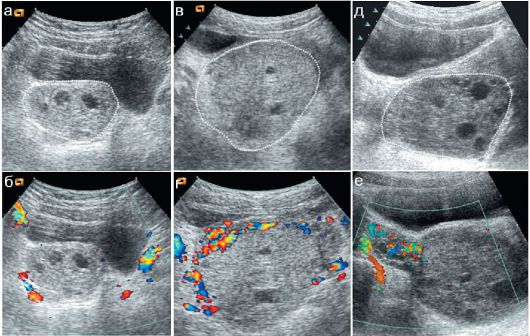

Не определяется яичник на узи

Не определяется яичник на узи 116 фото